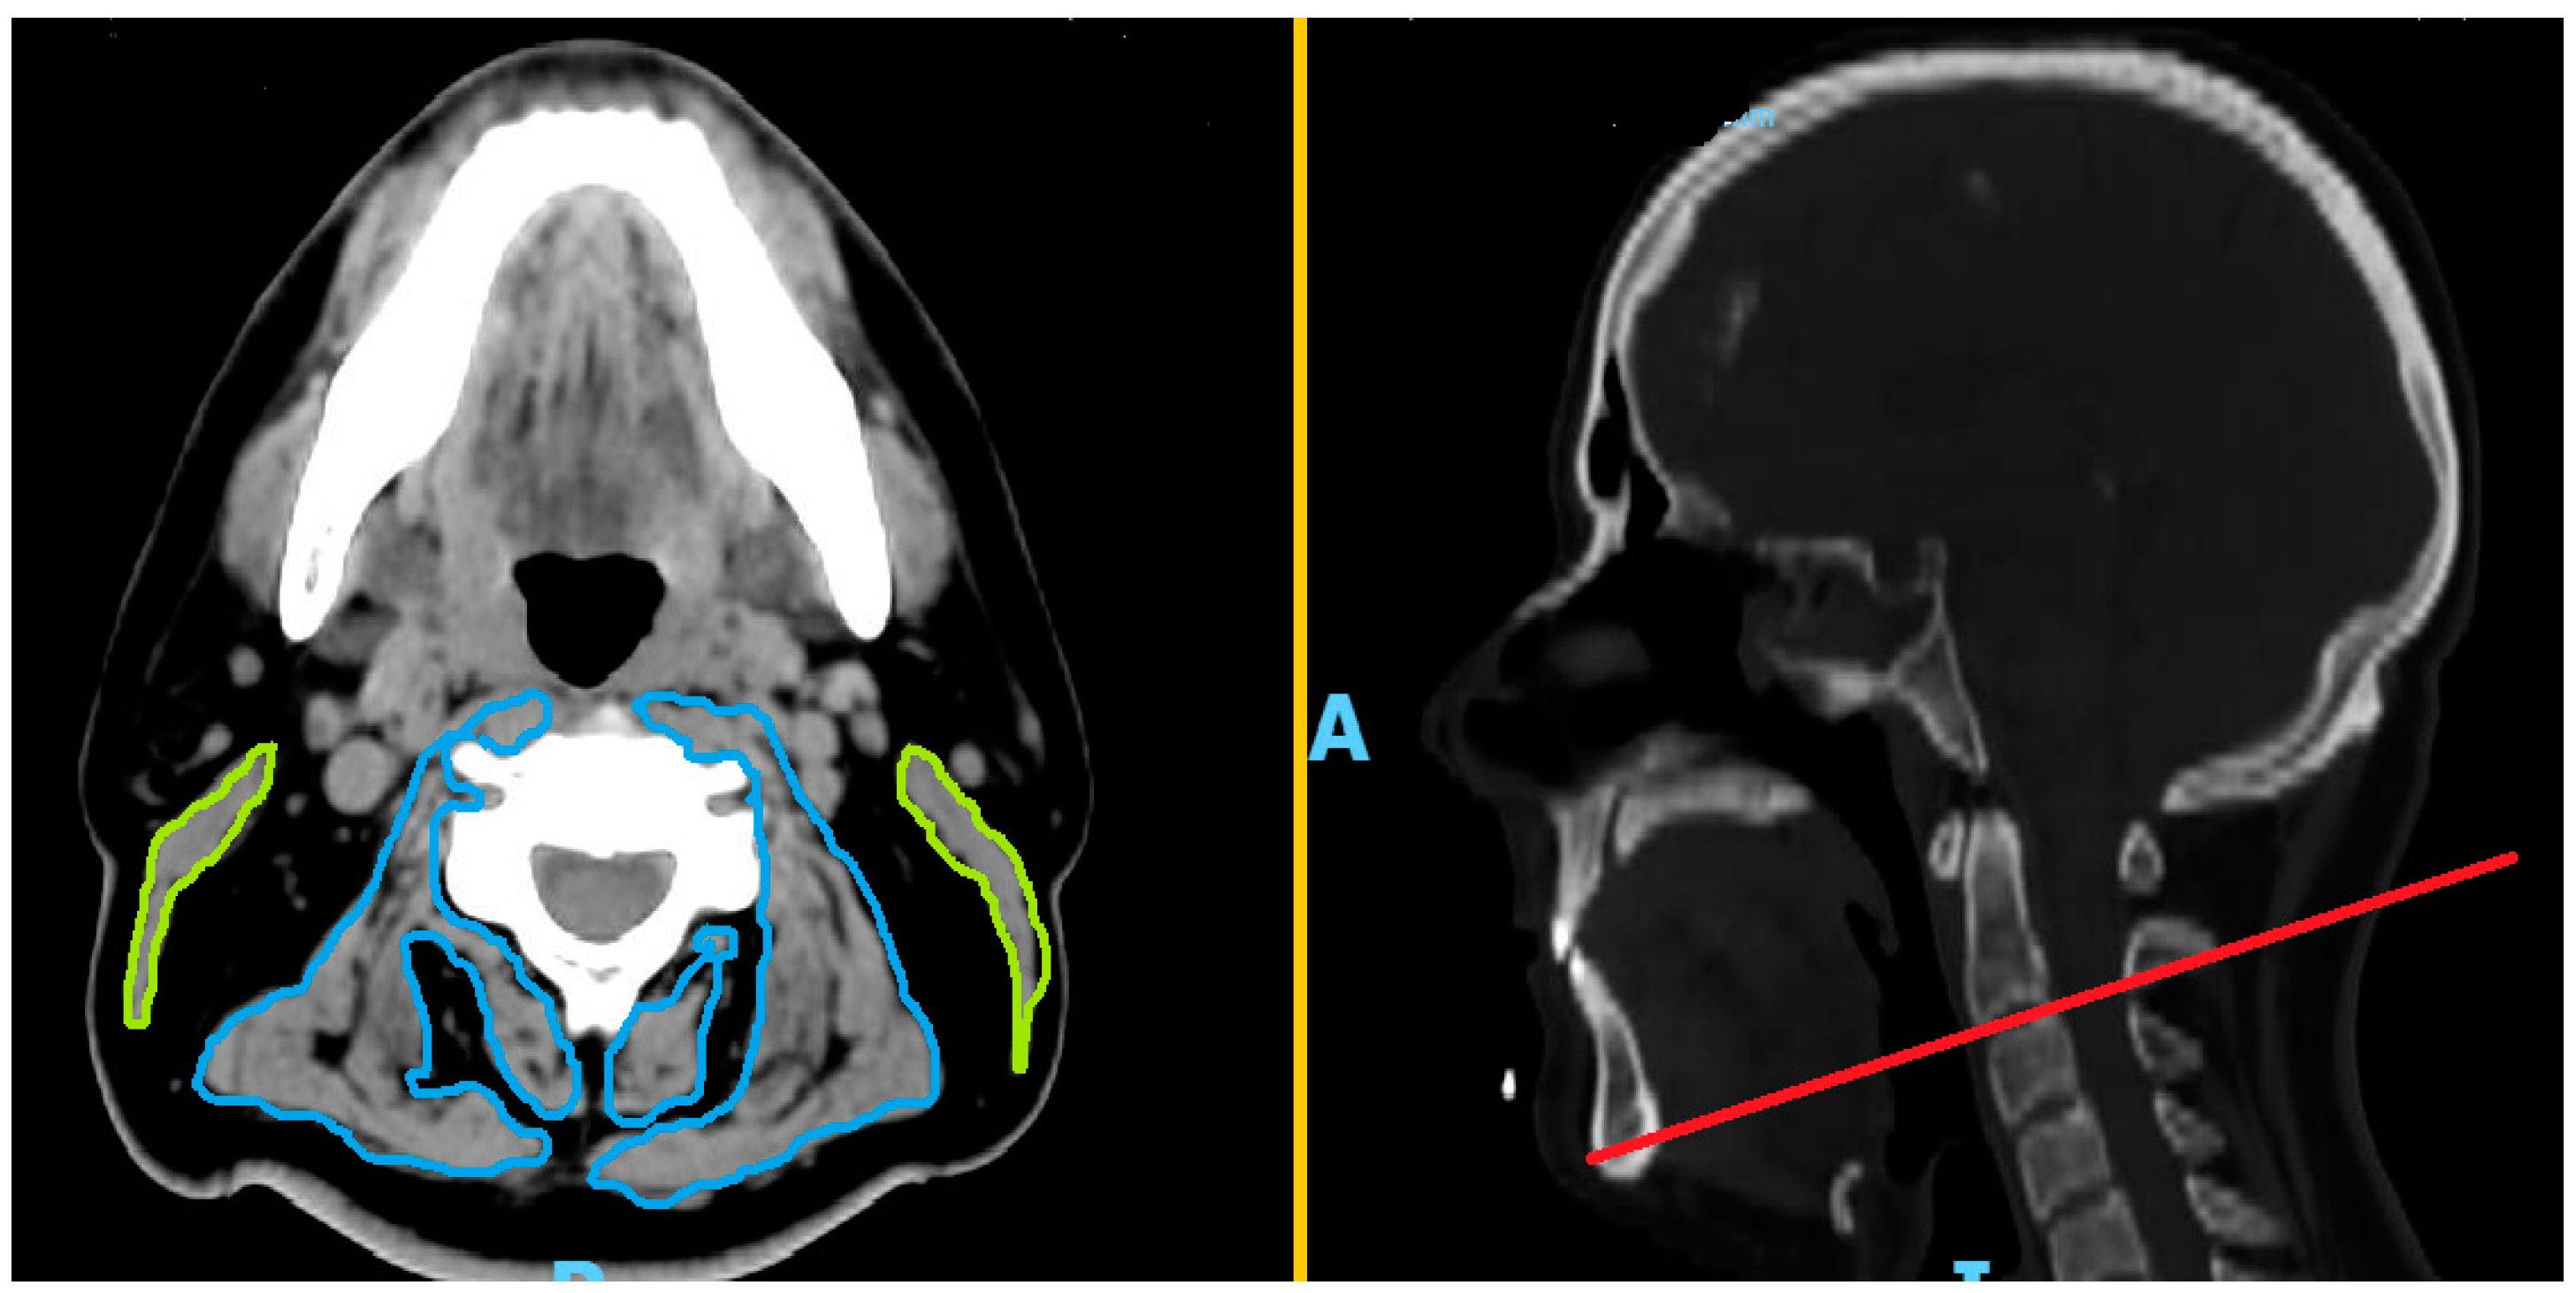

2. Materials and Methods

- Swartz, J.E.; Pothen, A.J.; Wegner, I.; Smid, E.J.; Swart, K.M.; de Bree, R.; Leenen, L.P.; Grolman, W. Feasibility of using head and neck CT imaging to assess skeletal muscle mass in head and neck cancer patients. Oral Oncol. 2016, 62, 28–33. [Google Scholar] [CrossRef] [PubMed]